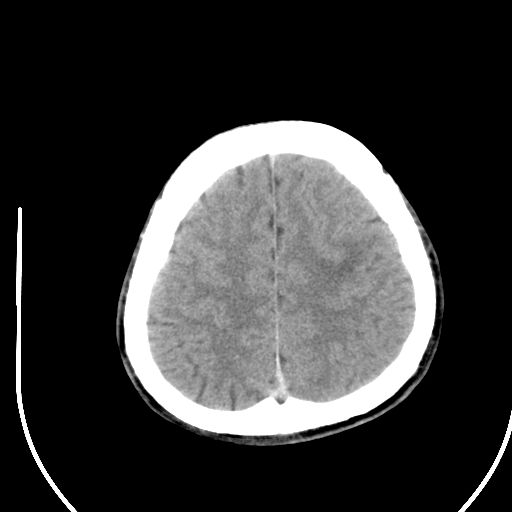

标题: CT28158:男,27Y。头痛数月,左顶叶血管瘤。 [打印本页]

标题: CT28158:男,27Y。头痛数月,左顶叶血管瘤。

考虑左顶叶海绵状血管瘤,建议mr检查。

左侧额叶海绵状血管瘤可能性大;建议行mri检查。

考虑血管畸形,因其周可见水肿,不除外感染性病灶。建议mri检查。